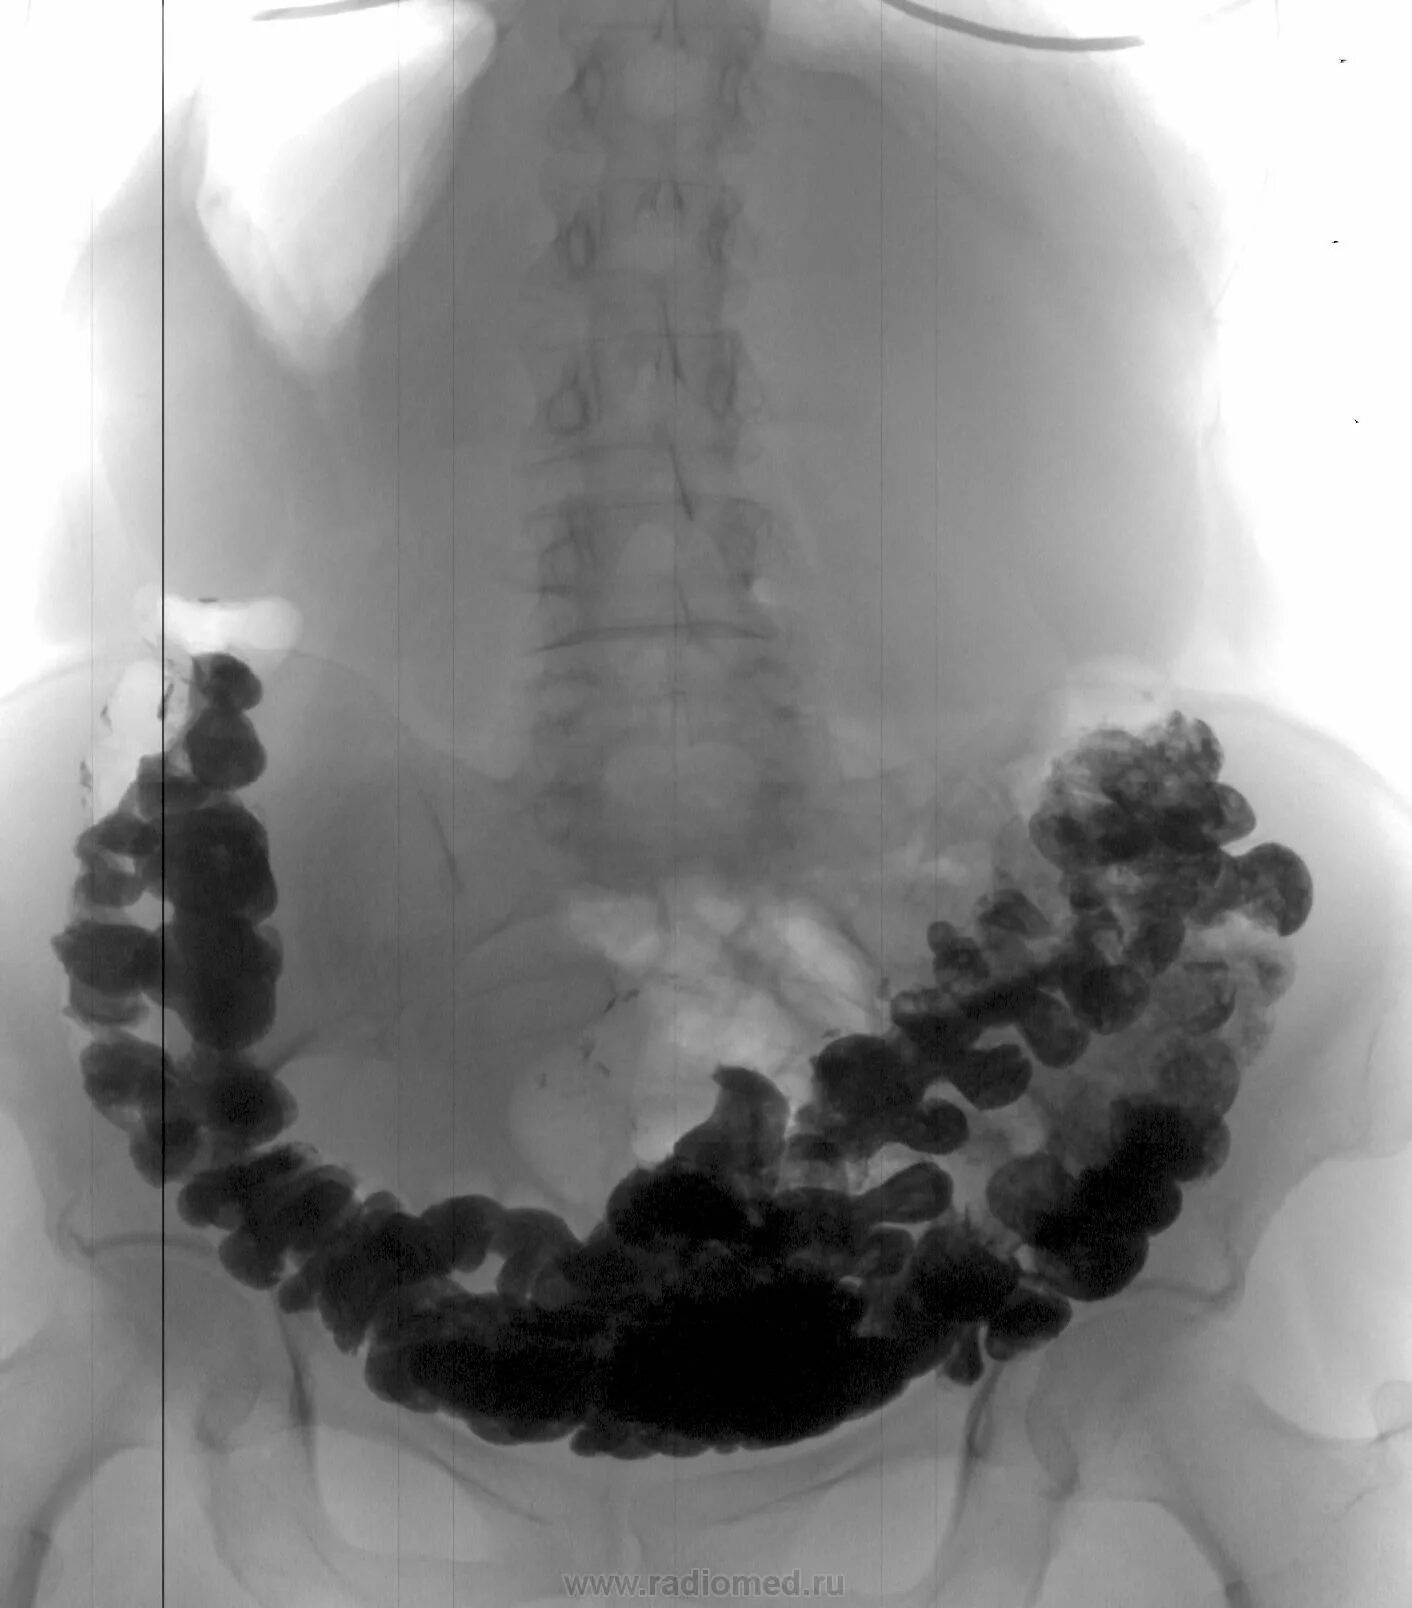

Синдром раздраженного кишечника толстой кишки симптомы. синдром раздраженной кишки. толстой кишечник болить.

Колит кишечника колоноскопия. неспецифический язвенный колит. язвенный колит кишечника симптомы.